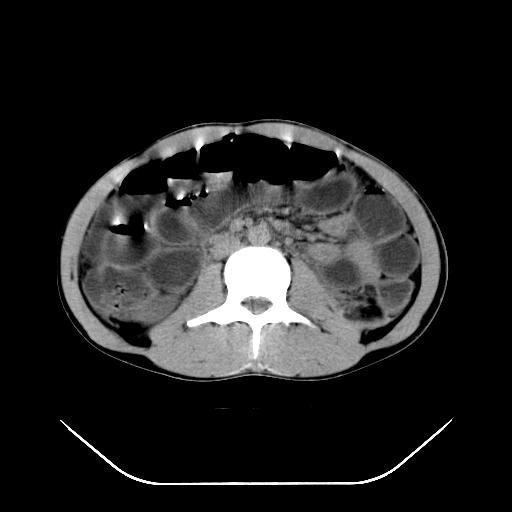

m-25y 高空堕落 12 月5号

12月7号病人尿量200ml/24h 急查双肾ct

顺便请各位老师认真看看7号片

各位老师觉得胆囊是不是有点积血。我在原始片看胆囊密度不均,似有小液平面

再有就是支持楼主,胆囊7日片比5日片不仅增大许多,靠后下更见液液分层,应该是有积血。

尽管上诉资料说的是b超,但其原理也同样使用于本例病人。12-05片胆囊没有问题,12-07却有类似于出血的高密度,不能 不说是非常奇怪和匪夷所思的现象。特意摘录出来与大家共勉,至少我们在诊断胆囊结石或出血的时候应该划过这样的印象。